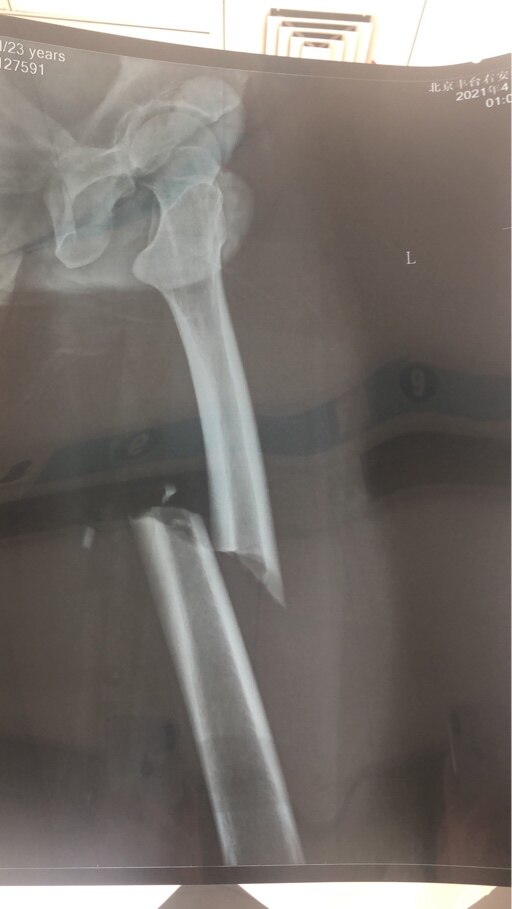

就你这个骨根本就不需要手术,我以前右手臂两根骨头摔断了也没有手术,找个接骨中医复位休息两个月就好了!不明白西医为什么一个小问题非得手术!

苏小末 发表于 2021-08-31 07:10

听你说的我有些哭笑不得,意思我这个不手术可能还可以自愈,算了,手术痛苦我能忍,这么严重不治疗估计得废了我一条腿

我今年4月份在北京车祸骨折

我也同款骨折,9月准备取钢板,无比害怕中,,,祝早日康复,其中酸爽,冷暖自知

苏小末 发表于 2021-08-31 11:57

你这个看起来挺严重的

重庆-江小白 发表于 2021-08-31 23:37

对啊。不过现在不用拐能走路了